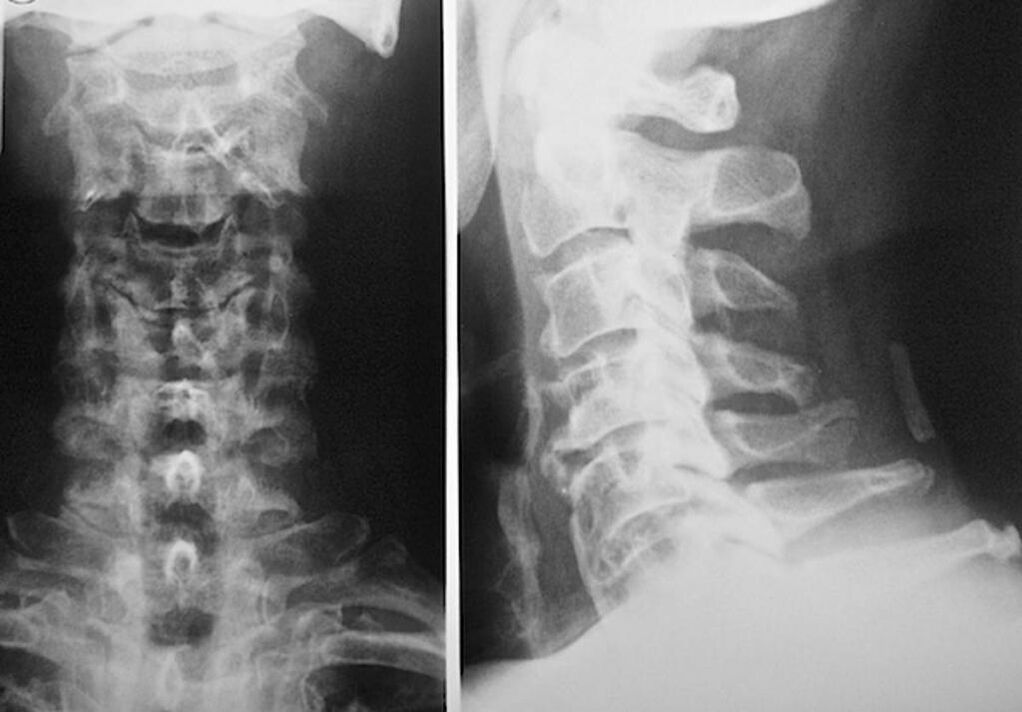

To diagnose and prescribe treatment for cervical osteochondrosis, you should sign up for consultation with a neuropathologist and an orthopedic surgeon. A neurologist can prescribe remedies for disease manifestations that affect the state of nerve endings. This makes sense if the disease is accompanied by radicular syndrome. An orthopaedic surgeon will assess the condition of the spine and diagnose the presence of other conditions: scoliosis, lordosis, etc.

To diagnose and accurately assess the condition of the intervertebral disc, the following research methods are used:

- radiography.

- CT scan.

- Magnetic tomography.

- Ultrasound scan of blood vessels in the neck.

Each of them is completely safe for health and poses no threat of overexposure. The diagnosis of cervical osteochondrosis, the treatment of which will occur for the rest of your life, can be made after a simple visual examination. Any orthopedic surgeon can easily do this. An exception is the first stage of the disease, when no visible lesions in the cervical region are found.